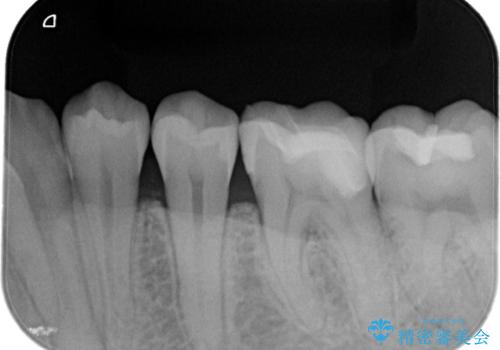

- 定期検診にて金属の下に虫歯を認めた患者様です。

拡大鏡を用い丁寧に虫歯を除去した後セラミックインレーにて修復治療を行っております。

修復物の適合は虫歯の再発リスクに影響する大切な要素です。